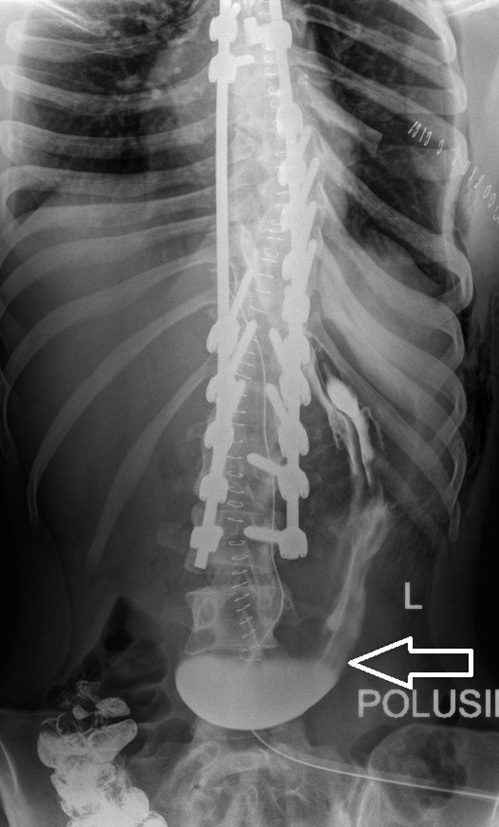

X-ray control was performed with the administration of a contrast agent through the duodenal probe (Fig. 4), which revealed restriction of the proximal distribution of the contrast agent with a clear, even vertical border at the level of the middle part of the horizontal loop of the duodenum.

Fig. 4. X-ray of the abdominal organs with the introduction of contrast through the duodenal probe

An intestinal probe under the control of an endoscope was inserted behind the area of the duodenum narrowing.

After a twofold change in body position (left side — back), a repeated X-ray control was performed (Fig. 5), which revealed the spread of the contrast agent into the jejunum. The introduction of the mixture into the duodenal probe was resumed. The mixture was absorbed completely without retrograde ingestion in the stomach.

Fig. 5. Repeated X-ray of the abdominal organs